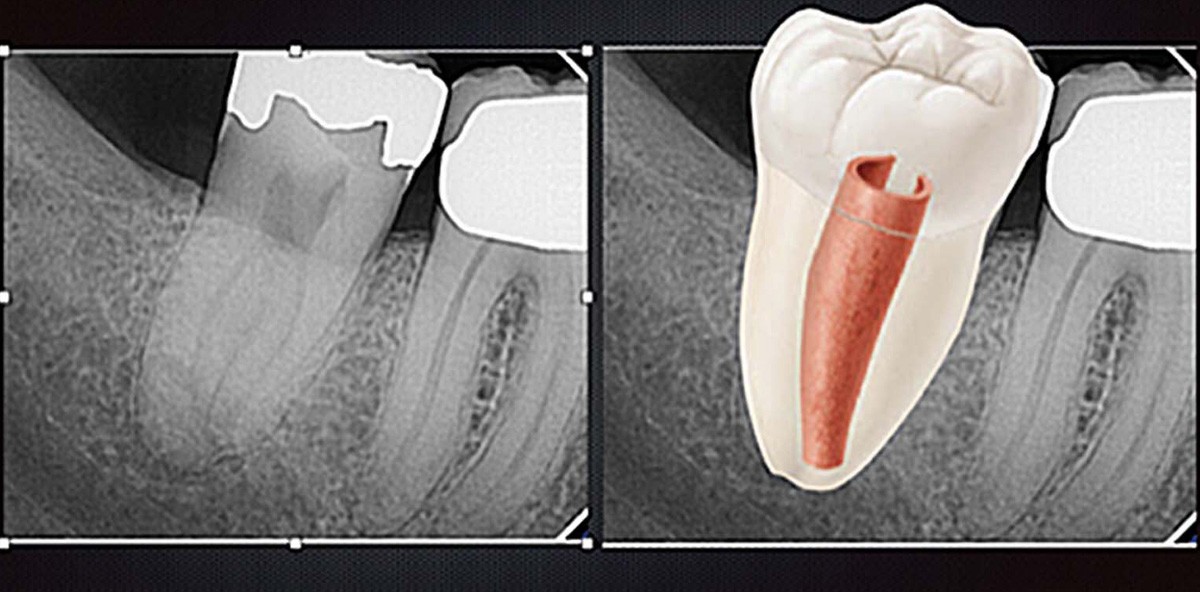

Zähne mit einer c -förmigen Kanalkonfiguration sind in sehr vielen morphologischen Variationen zu finden. Die am häufigsten verwendete Klassifikation von Melton et al. ist in der Abbildung 1 aufgeführt. Eine „klassische“ c -förmige Kanalkonfiguration hat einen durchgängigen Isthmus, der die Form eines „c“ hat, wobei die Rundung meist bukkal liegt. Dieses Muster folgt vollständig oder teilweise bis zum Apex. Eine andere häufige Konfiguration beinhaltet ein Dentinband an einem Ende des Isthmus. Die Form ähnelt einem Semikolon. Eine weitere Konfiguration zeigt einen mesialen und/oder distalen Kanaleingang wie in einem üblichen Molaren und einem schmalen Isthmus (Abb. 2). Eine weniger häufige Konfiguration ist ein symmetrisch angelegter mesialer und distaler Kanaleingang im Oberkiefermolar. Ein Isthmus ist nicht vorhanden, aber es zeigt sich eine aus mehreren Wurzeln verschmolzene Wurzel.

Die meisten Zähne mit einer c -förmigen Kanalkonfiguration sind mit einer Einzelzahnaufnahme zu identifizieren (Abb. 3). Die Wurzeln sind fusioniert und zeigen eine konische Erscheinung. Die Wurzelkanäle vereinigen sich kurz vor dem Apex. Ist man trotzdem nicht sicher, ob es sich um eine c -förmige Wurzelkonfiguration handelt, dann ist die Erstellung einer DVT-Aufnahme sinnvoll. Mit der horizontalen Darstellung lässt sich die Kanalkonfiguration sehr gut bestimmen. Die Wanddicke und die Dimension der Pulpa lassen sich ebenfalls gut einschätzen und sind somit für die Behandlungsplanung sehr hilfreich. Bei der klinischen Untersuchung müssen alle Tests (Sensibilität, Perkussion, Palpation etc.) durchgeführt werden, um den Zustand der Pulpa und des periradikulären Bereiches bestimmen zu können. Ebenso wichtig ist die Messung des parodontalen Zustandes. Wegen der schwierigen Behandlung von Zähnen mit einer c -förmigen Wurzelkanalkonfiguration sollte bei einer ausgeprägten parodontalen Erkrankung sehr genau überlegt werden, ob eine endodontische Behandlung des Zahnes noch sinnvoll ist.